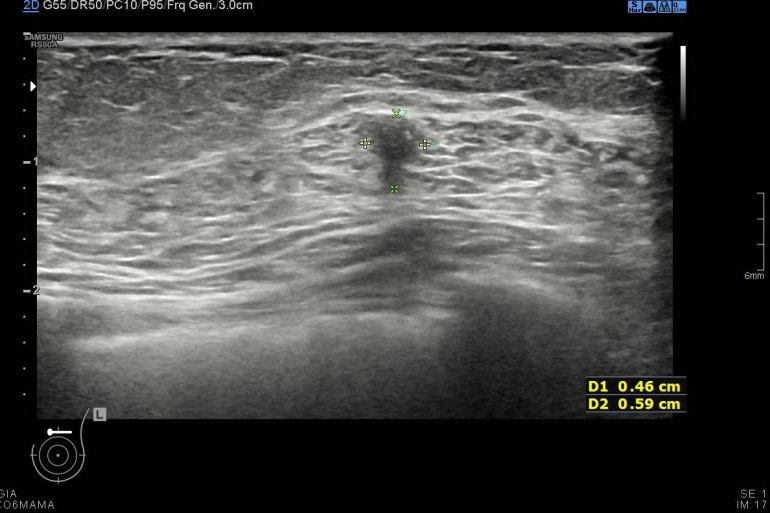

Durante la exploración se observan cambios secundarios a mastectomía bilateral, pero en línea intercuadrántica superior de mama izquierda, en el espesor del musculatura pectoral vi un nódulo hipoecogénico de 6 mm de bordes irregulares (imágenes 2 a 5) que me pareció muy feo, me asusté y aunque no era palpable inmediatamente se lo comenté a la doctora encargada de la exploración, lo calificó de Birads 4C y le pidió resonancia magnética.

Tras los estudios posteriores realizados como ampliación de estudio, arrojaron cambios postquirúrgicos en el pectoral que explicaban la imagen descrita anteriormente y que puedes ver en la imágenes que te he puesto.

Afortunadamente fueron buenas noticias, el resultado fue benigno a pesar de la alta sospecha, a consecuencia de los cambios posquirúrgicos que afectaban a la porción muscular de la exploración ecográfica. Siempre en mamas operadas los cambios postquirúrgicos pueden ofrecer zona llamativas, nosotros siempre atentos y ante cualquier duda lo dejamos reflejado en el pre-informe o se lo contamos directamente a la radióloga responsable, nunca nos quedamos con dudas, siempre documentar los hallazgos correctamente con máxima calidad de imagen, siempre es nuestra carta de presentación.